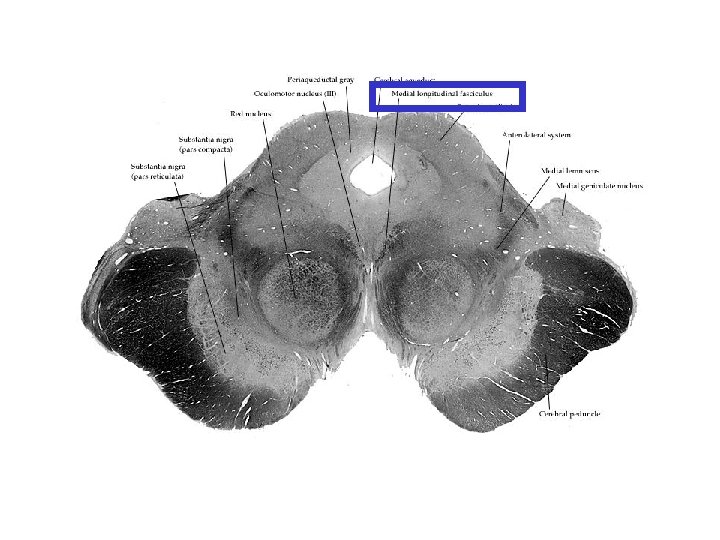

Fasciculus longitudinalis medialis Orta çizgiye çok yakın olarak yer alır. Kafa çiftlerinin birbirleri ile olan bağlantısını sağlar Beyin sapında göz kaslarını inerve eden çekirdekler arasında ve bu çekirdekler ile vestibular sistem arasında önemli rol oynar.